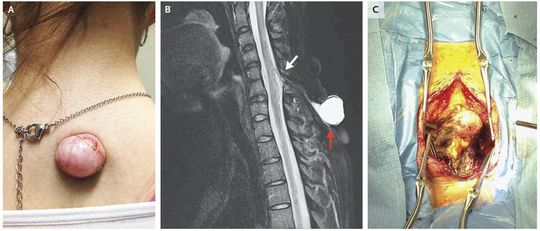

A healthy 22-year-old woman presented with a posterior cervical midline cutaneous lesion that had been present since birth and had been growing for years. The patient had undergone repeated aspirations, with no history of meningitis or myeloradiculopathy. Physical examination revealed a partially spherical lesion that was 2.5 cm in diameter (Panel A), compressible, and nontender, with no active leakage. Neurologic examination was significant for Hoffmann’s sign bilaterally and evidence of an upper motor neuron lesion affecting both shoulders, arms, forearms, and hands. Magnetic resonance imaging revealed a fluid-filled, dorsal cutaneous lesion (Panel B, red arrow) and dorsal spinal cord tethering (white arrow), with a connecting tract. Cervical meningoceles are uncommon neural-tube defects. The recognition of spinal dysraphic conditions in adults can prevent infectious and neurodegenerative sequelae. The patient underwent posterior cervical exposure of the lesion and spine, laminectomy, fibrous-stalk resection, spinal cord detethering, and expansile duraplasty (Panel C). She had no neurologic deterioration or cerebrospinal fluid leak in the hospital and was discharged home. At last follow-up, she had no visible recurrence of the cutaneous lesion and no evidence of neurologic evolution of cervical myelopathy or radiculopathy.